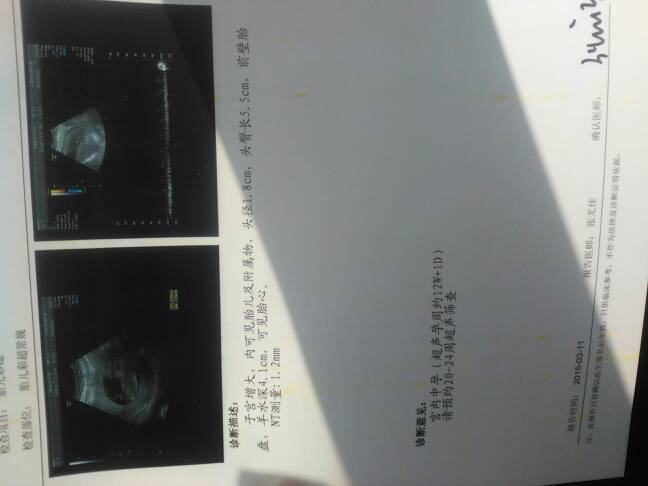

请医生们帮我看看,十二周了,这个B超胎儿发育正常吗?谢谢了 请医生们帮我看看,十二周了,这个B超胎儿发育正常吗?谢谢了 点击展开 135*****879_SKaM 2015-03-11 14:14 为您推荐: 其他回答 正常的,6个月可以在做一次检查更清楚点 AliceAlxe 2015-03-11 17:27 正常.... 谷雨_8rr1 2015-03-11 15:09 正常。。。 一见不钟情_Ndqe 2015-03-11 14:25 祝宝妈好孕 187*****528_bXRy 2015-03-11 14:17 正常的!!! 林晨妈咪! 2015-03-11 14:17 加载更多 相关问题 有医生可以帮我看看胎儿发育怎么样,正常不正常啊 今天做b超结果宫内胎儿BPD5 4cm胎儿一侧脑室宽约0 8cm医生说胎儿发育不正常说脑室太宽我应 我怀孕50天的时候去做的B超,医生说胎儿发育有点晚,只有一个月大,给开了安胎口服液,叶酸还有维生素